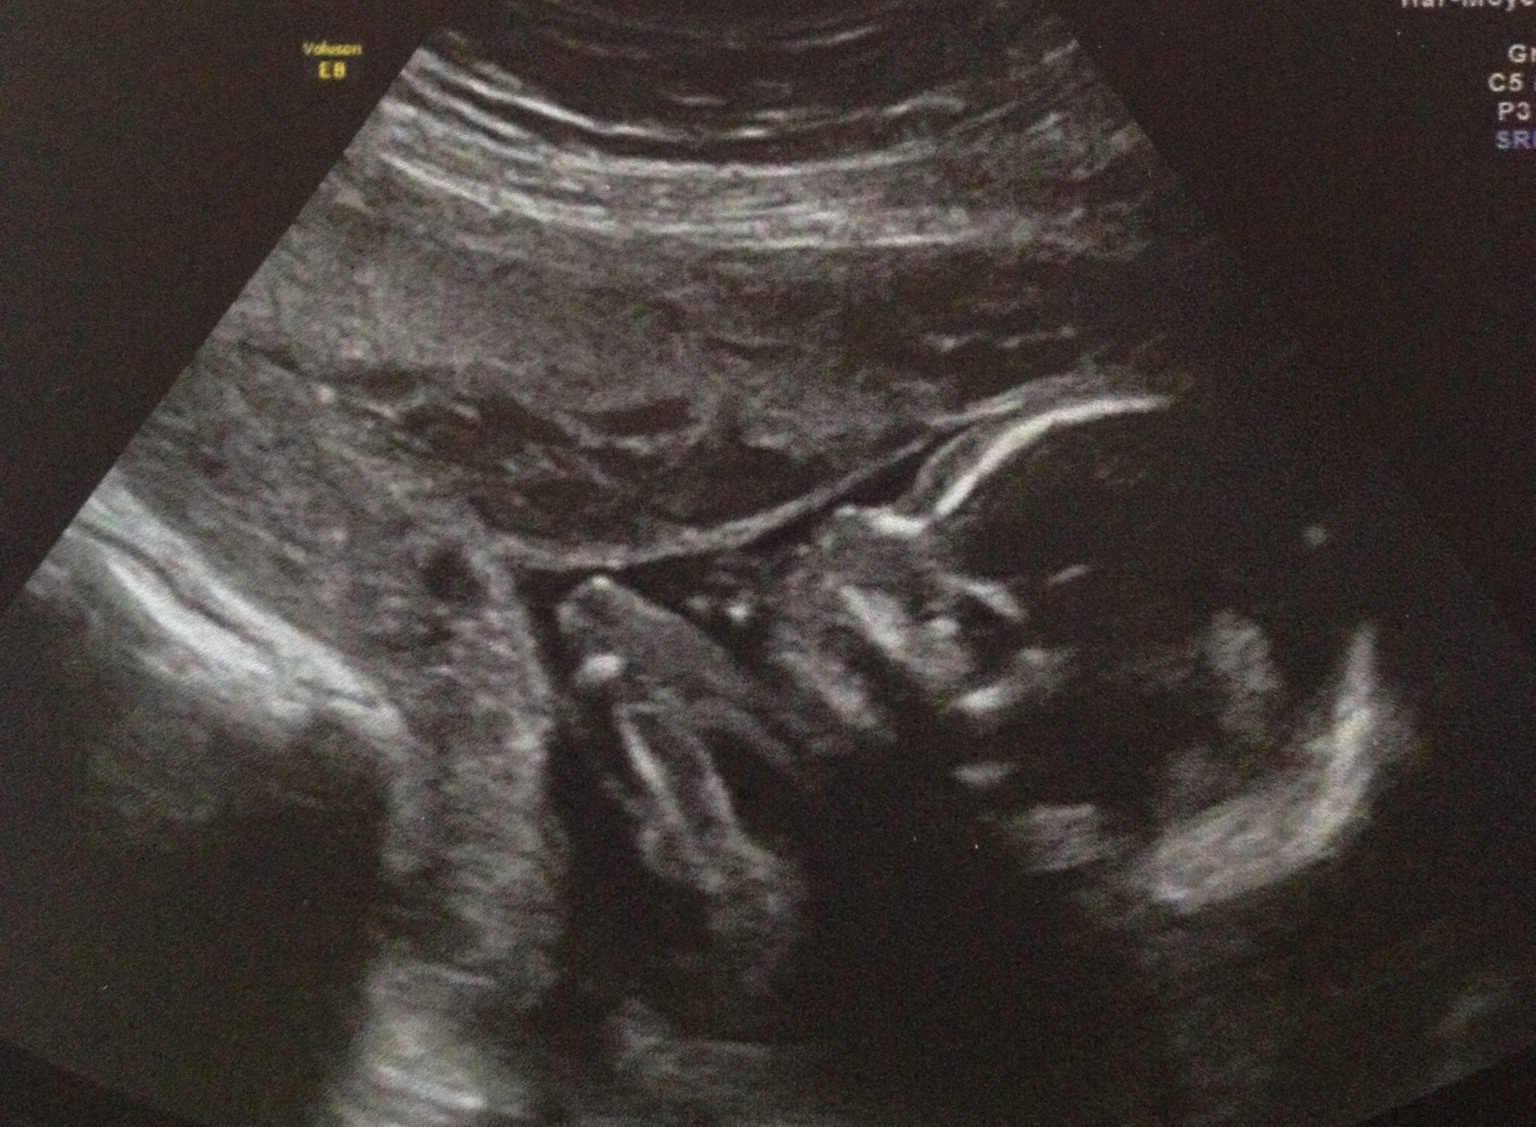

Mon fils n'aime pas les photos donc bon je pourrais pas vous montrer grand chose lol. Voilà son profil et son dos fesses et jambes lol. Mais a L'Echo on a trop bien vu sa bouche son nez des petit pieds ses petites mains fin génial ;)